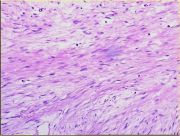

| 2021年12月10日 (五) 13:15 | 13号切片-纤维瘤-镜下观2.jpg (文件) |  |

175 KB | Cirno.9 | 基于MsUpload的文件上传 | 1 |

| 2021年12月10日 (五) 13:15 | 13号切片-纤维瘤-镜下观1.jpg (文件) |  |

174 KB | Cirno.9 | 基于MsUpload的文件上传 | 1 |